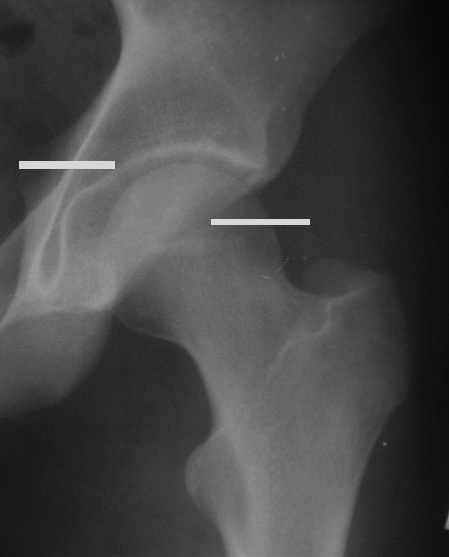

Уважаемые коллеги! Заканчивая обследование больного с переломо-вывихом бедра сделал ему обычные R-томограммы. Кажется удалось "поймать" и отломок и донорское место. Мои выводы - в скиаграмме. Считаю, что это передне-нижний фрагмент головки, образовавшийся вследствии отрывного перелома. На томограммах отломок обозначаю длинной стрелкой, а место откуда он оторвался - более короткой. Учитывая тот факт, что его размеры по КТ 25 х 15 мм считаю, что его фиксация на место необходима для профилактики артроза, что при 16-ти летнем возрасте пациента важно в плане максимального отодвигания эндопротезирования. Планирую оперировать его 24.05.05 г. Результаты представлю.

Прямой при поступлении

Прямой 19.05

Несколько соображений к "картинкам". На прямом снимке и КТ-томограммах все типичные линии вертлужной впадины: крыша, передняя стенка, задняя стенка - сохранены. На КТ-сканах 6 и 7 появляется фрагментация головки. С учетом R-томограмм отломок расположен спереди-снизу, а не сзади-сверху от сустава, как написано в описании КТ.